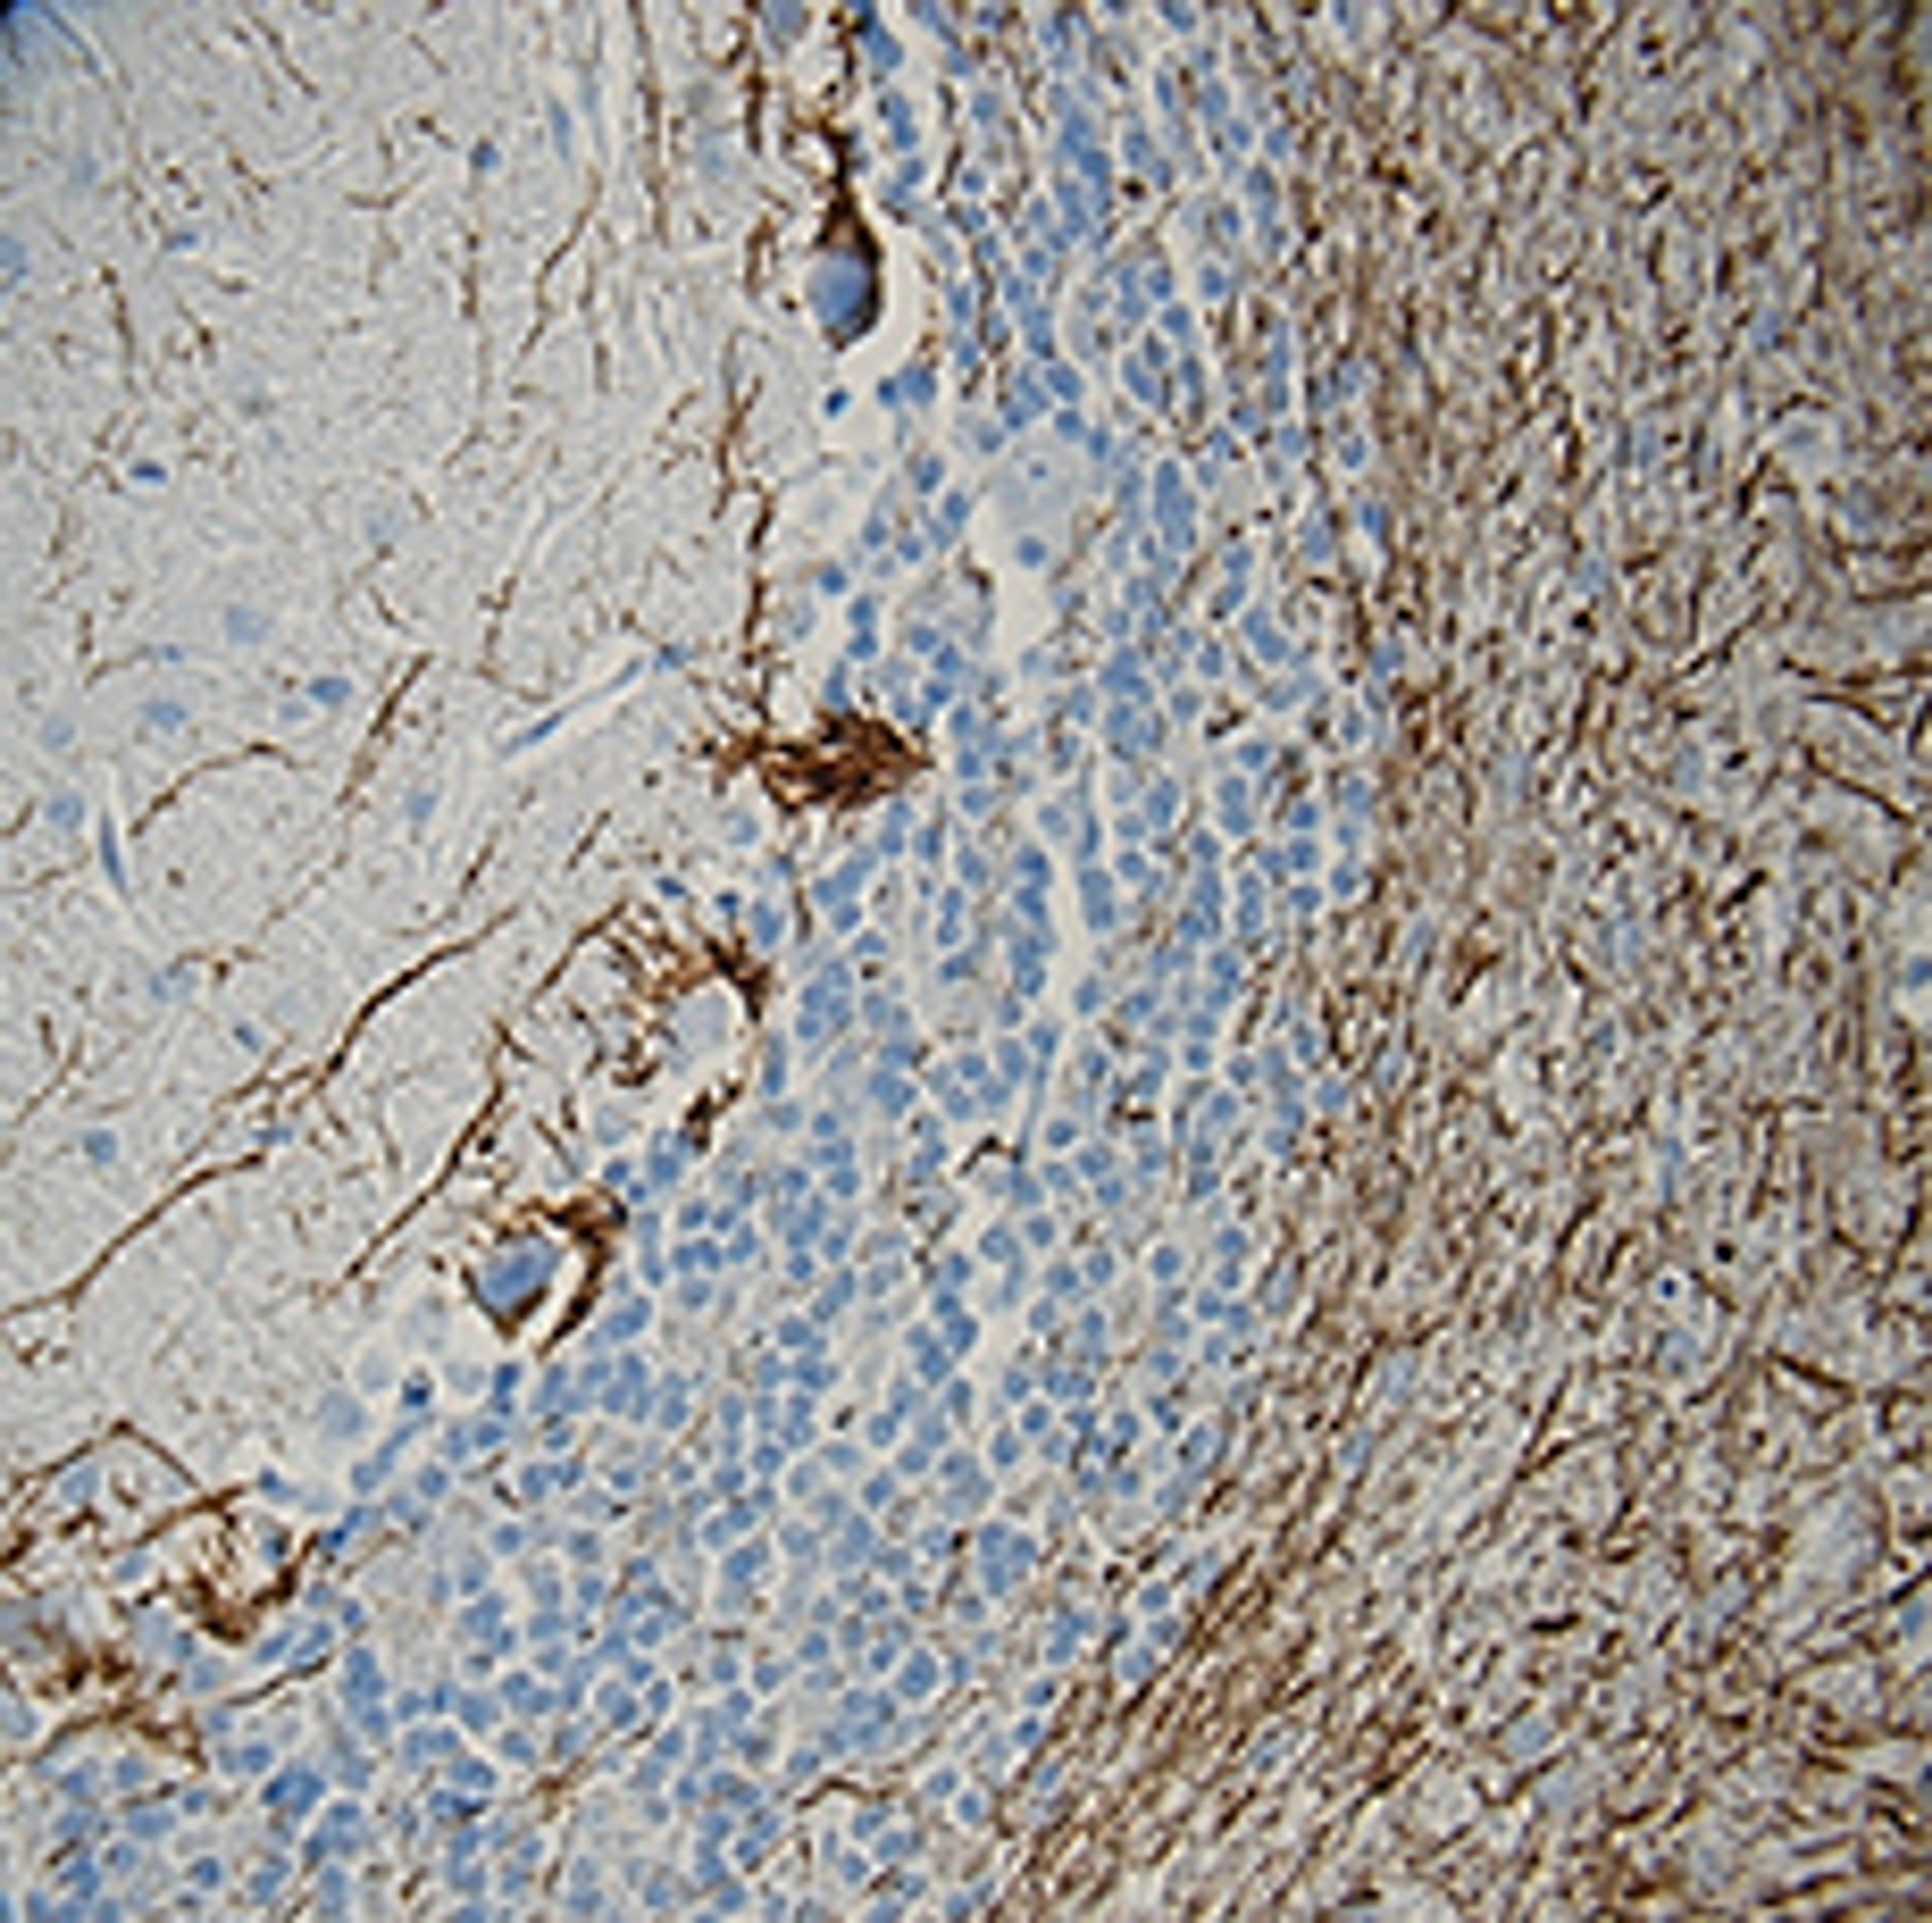

Purified anti-Neurofilament H (NF-H), Phosphorylated; Clone: SMI 31; Reactivity: Mammalian, Chicken, Xenopus; Apps: IHC, WB, ICC, ELISA; Size: 100 μl

- Immunohistochemistry (IHC)